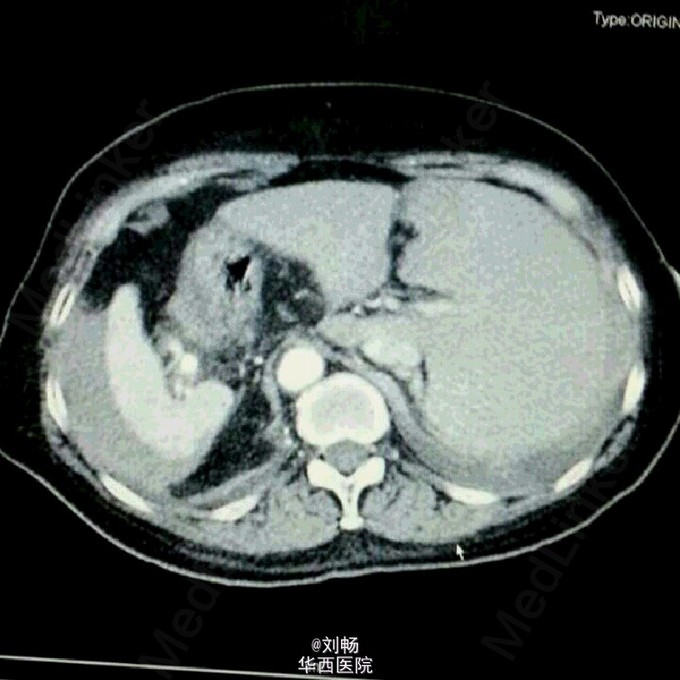

遭遇镜像人!

“镜像人”,学名:全脏器反位。患者老年女性,自发性腹痛3天,入院考虑自发性脾破裂,全脏器反位。术中证实脾动脉瘤,脾破裂。术中照片也秀一下。记住:你的心脏在左边,他的心脏在右边,当他摸着右边胸口对你发誓的时候,并不是在忽悠你哦。

“镜像人”,学名:全脏器反位。患者老年女性,自发性腹痛3天,入院考虑自发性脾破裂,全脏器反位。术中证实脾动脉瘤,脾破裂。术中照片也秀一下。记住:你的心脏在左边,他的心脏在右边,当他摸着右边胸口对你发誓的时候,并不是在忽悠你哦。